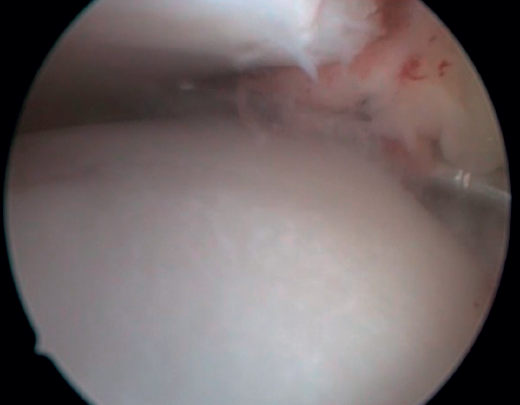

Bony AAI due to osteophytes has also been linked to the presence of chronic instability. It has been postulated that altered joint kinematics secondary to ligament insufficiency favors the development of osteophytes in the anterior region of the tibia and talus(36,37). Recent studies have questioned the theory of repeated capsular traction as the origin of osteophytes in sports(38), as it is easily demonstrated that osteophytes are located intra-articular within the capsular insertion, in the context of ankle arthroscopy (Figure 2). Therefore, ankle dorsiflexion arthroscopy is essential to safely resect osteophytes without damage to the capsule or overlying structures, whereas the classical traction technique (invasive or otherwise) would make resection extremely difficult, and is thus not recommended nowadays for routine use(3,39). Vega distinguished between two types of osteophytes(3), according to whether they are caused by repetitive trauma (peak-shaped) or instability (visor-shaped). The concept of micro-instability is associated with repetitive micro-trauma, which could be the origin of osteophytes with this characteristic morphology (Figure 3).

Resection of the osteophyte is performed by displacing from the top, and gradually reducing it until the joint zone is reached (Figure 2). A basket forceps can be used to resect the area closest to the joint (Figure 5). It is often useful to exchange the viewing and working portals in order to visualize and completely resect the osteophytes. In the case of soft tissue impingement, a 3.8 or 4 mm synoviotome is usually sufficient. The vaporizer is useful in the case of compact impingements, typical of post-traumatic conditions or re-interventions, and also for delimiting the bony part of the osteophyte before resection.